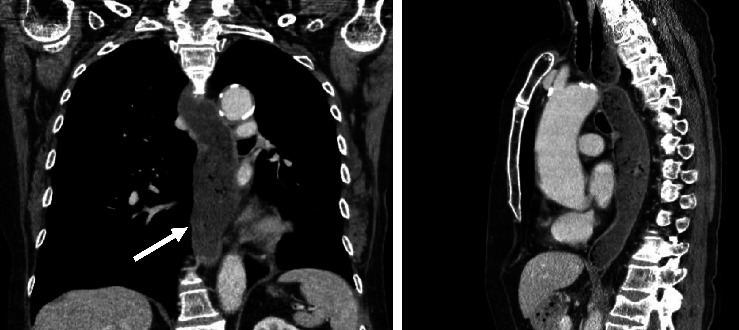

背景:假性失弛缓症是一种罕见的抗胡相关综合征的表现。我们提出的情况下,61岁的女性患者主要表现为进行性疼痛和四肢感觉障碍。原发性治疗反应后神经系统症状进展,神经抗胡抗体检测呈阳性,这通常是副肿瘤综合征的替代指标。随后,在反复成像后,切除了肺类癌,术后未发现复发。首次神经系统症状出现近90个月后,患者出现吞咽困难,通过食管测压法诊断为假性失弛缓症。由于气动扩张后复发,经内镜注射肉毒杆菌毒素对患者的临床效果很好。目的:本病例说明抗胡相关的副肿瘤假性失弛缓症可能发生在临床过程的后期,提示抗胡阳性个体新发吞咽困难应通过影像学、内窥镜检查、测压和组织学进行彻底调查。

Background: Pseudoachalasia is a rare manifestation of anti-Hu-associated syndrome. We present the case of a 61-year-old female patient presenting primarily with progressive pain and sensory disturbance of all limbs. Neurological symptoms progressed after the primary treatment response and onconeural anti-Hu-antibodies were tested positive, which is often a surrogate to paraneoplastic syndrome. Subsequently, after repeated imaging, a lung carcinoid tumor was resected without detectable recurrence after surgery. Nearly 90 months after the first neurological manifestation, the patient developed dysphagia and the diagnosis of pseudoachalasia was established by esophageal manometry. Due to recurrence after pneumatic dilatation, endoscopic botulinum toxin injection provided good clinical results for the patient. Purpose: This case illustrates that anti-Hu-associated paraneoplastic pseudoachalasia may occur late in the clinical course, indicating that new-onset dysphagia in anti-Hu-positive individuals should be thoroughly investigated by imaging, endoscopy, manometry, and histology.